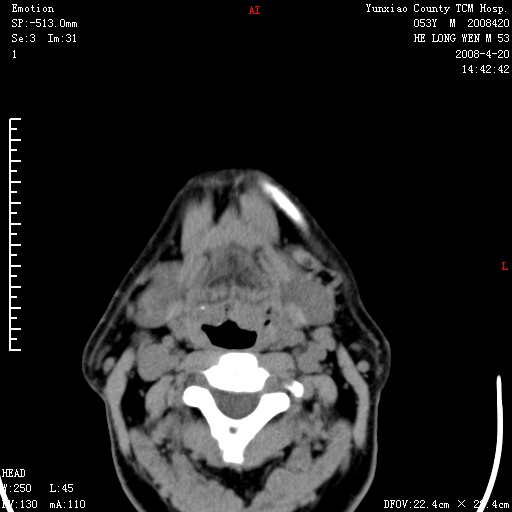

双侧扁桃体肿大:考虑化脓性扁桃体炎。

双侧扁桃体肿大 ,考虑扁桃体炎。

双侧扁桃体肿大,建议结合临床!

双侧扁桃体肿大 ,考虑扁桃体炎

应该有症状,体检此部位不是常规体检项目,支持双侧扁桃体肿大 ,考虑扁桃体炎,但还是强化一下吧。

双侧扁桃体肿大,考虑扁桃体炎,应做一下增强

显示部分为舌扁桃体,腭扁桃体未见显示。会厌显示欠规则,建议喉镜。